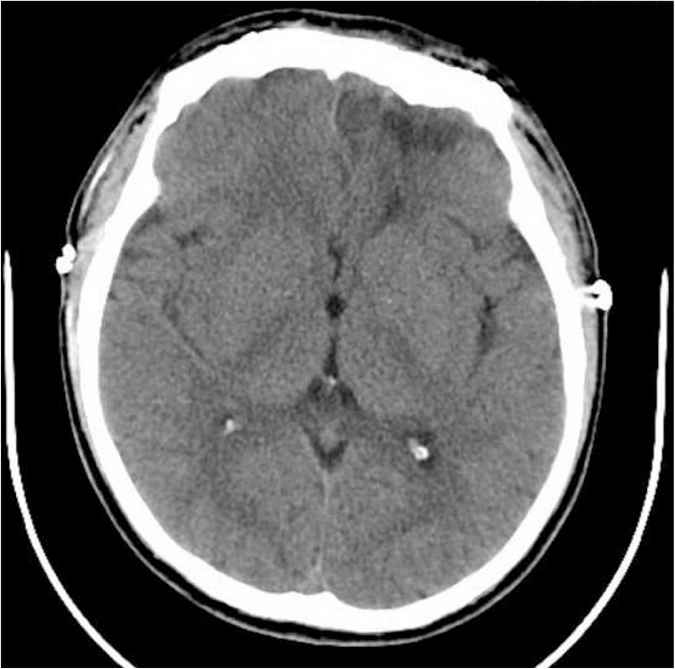

A 34-year-old gentleman presented to the emergency room complaining of sudden severe headache that started on the same day of his presentation. The headache was associated with frequent vomiting and clear fluid leakage from the left nostril. He had history of head trauma 3 months ago in another country, but did not require any surgical intervention as he claimed. Upon examination, he had normal vital signs. Results of his head examination revealed an old mild depression at the forehead region. His Glasgow Coma Scale (GCS) score was 15/15. Fortunately, his neurological examination was completely normal including the examination results of motor, sensory, cerebellar, and cranial nerves. His initial blood investigations were completely within the normal range. CAT scan was performed urgently and revealed a large area of encephalomalacia in the left frontal lobe filled with air, which communicated with the related frontal horn of the left lateral ventricle (Figure 1). A small defect was also seen in the posteroinferior aspect of the left frontal sinus, associated with multiple foci of PNC seen along the convexity of the brain, in the basal cisterns, and lateral and third ventricles as well. The CAT scan also showed an old depressed fracture of the left side of the frontal bone (depressed by 7.4 mm). Moreover, the volume of air in the intracranium cavity was estimated by the reporting neuroradiologist to be approximately 45 mL of air based on the patient’s CAT scan. The patient was urgently evaluated by the neurosurgical team and was taken on the same night for surgical repair. Accordingly, he underwent bifrontal craniotomy, repair of posterior sinus fracture, and recanalization of the frontal sinus. Postoperatively, he had an uneventful smooth recovery with rapid resolution of his headache. A repeat CAT scan of the brain was obtained and showed complete resolution of the PNC with small air foci noted in the right frontal horn of the lateral ventricle (Figure 2). On the 11th postoperative day, the patient was discharged home symptom-free.

Encephalomalacia in the left frontal lobe filled with air that communicates with the frontal horn of the left lateral ventricle.